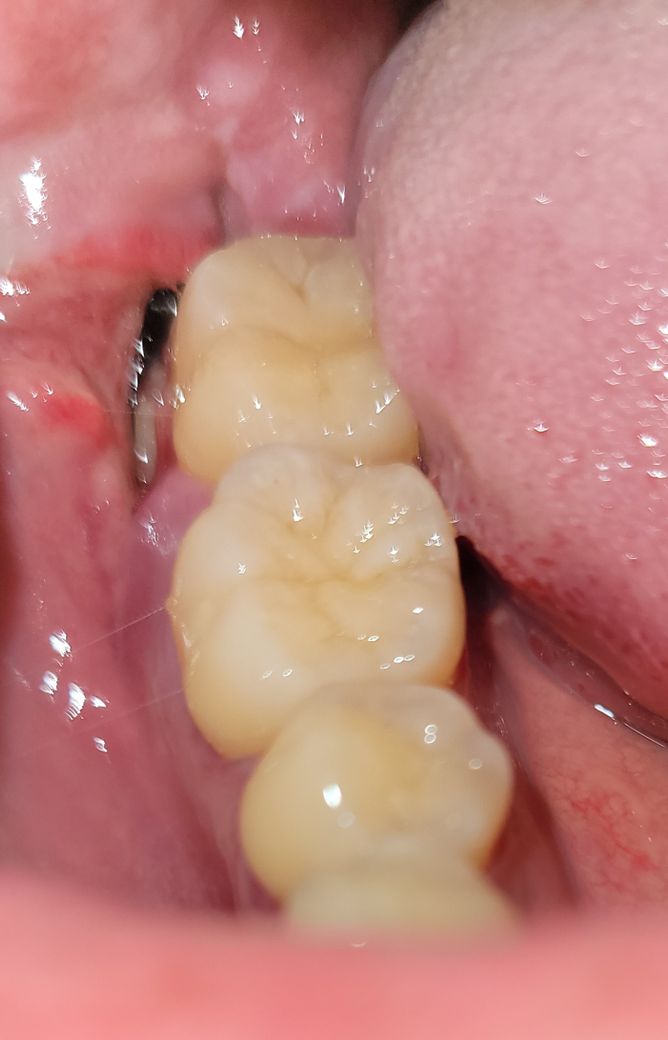

발치 후 일주일차 이거 괜찮은건가요?

오늘 1주일차 되었습니다.

실밥 풀러 병원갔는데 실밥이 없다면서 밥 드시다 없어지셨나봐요 이러셔서 소독만하고 왔습니다.

너무 깊은 홈이 있어요..

그리고 안에 움식물로 보이는 무언가와

안쪽에 검은색 뭔가가 깊이 박혀있는데

이게 뭔지 모르겠어요..

이거 괜찮은거 맞나요?

홈은 시간이 지나면서 자연스럽게 닫히게 됩니다 . 실밥이 빠지더라도 회복에는 상관은 없으며 잘 낫고 있습니다.

사진상으로 보면 검정색은 실밥인거 같은데 치과에 가셔서 다시 체크를 한번 받아보시는게 좋을것같습니다.

사진이 흔들려서 정확히 보이지는 않습니다만 단순 이물질일 것 같습니다. 보통 발치 후 잇몸 치유는 2주 정도 걸립니다.

상처가 완전히 아물지 못하면 이렇게 보이지만 시간이 지나면 점점 없어집니다. 실밥은 아닙니다.